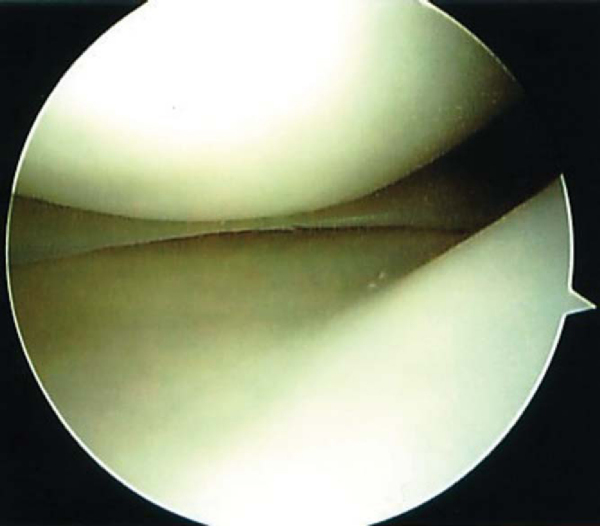

To enter the lateral compartment, a triangular space formed by the lateral border of the anterior cruciate ligament, the anterior horn of the lateral meniscus, and the lateral femoral condyle is identified. The arthroscope is directed into this space as the leg is placed into a figure-of-four position. An assistant can apply a varus stress by placing pressure on the medial aspect of the knee to open the joint further. The lateral meniscus is inspected and probed (

Fig. 42-6

). The popliteal tendon is seen passing through the popliteal hiatus. The leg is fully extended and flexed to assess the articular cartilage of the lateral compartment. If the scope is backed into the intercondylar notch with the knee in the figure-of-four position, the posterolateral bundle of the anterior cruciate ligament can be well visualized (

Fig. 42-7

).